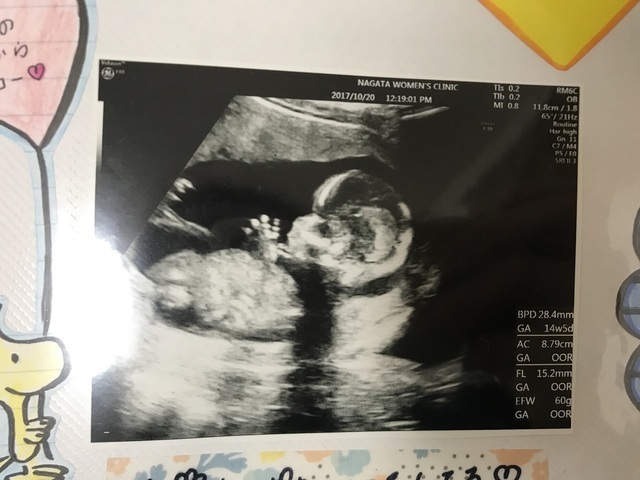

15週0日(15w0d・男の子)|もっきー さん(22歳)

エコー写真撮影時のエピソード:

この頃からポコポコと胎動を感じるようになってとても嬉しかったです。また、初めての腹部エコーでこんな可愛い姿を見れて、メロメロでした。旦那さんとニヤニヤ見つめていました。この手で目を隠してる姿、恥ずかしがり屋な子なのかな?と私に少し似てるのかな?って思ってしまいました。